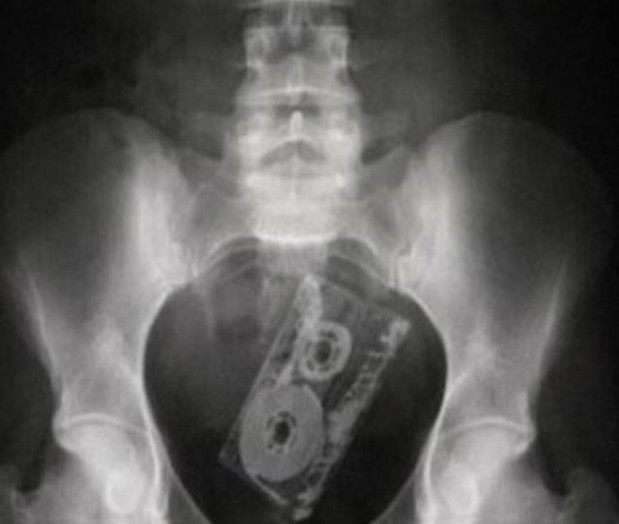

#13 VHS-kasetti